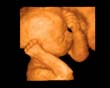

3-D Technology Helps Expecting Mothers Discover Their Unborn Children